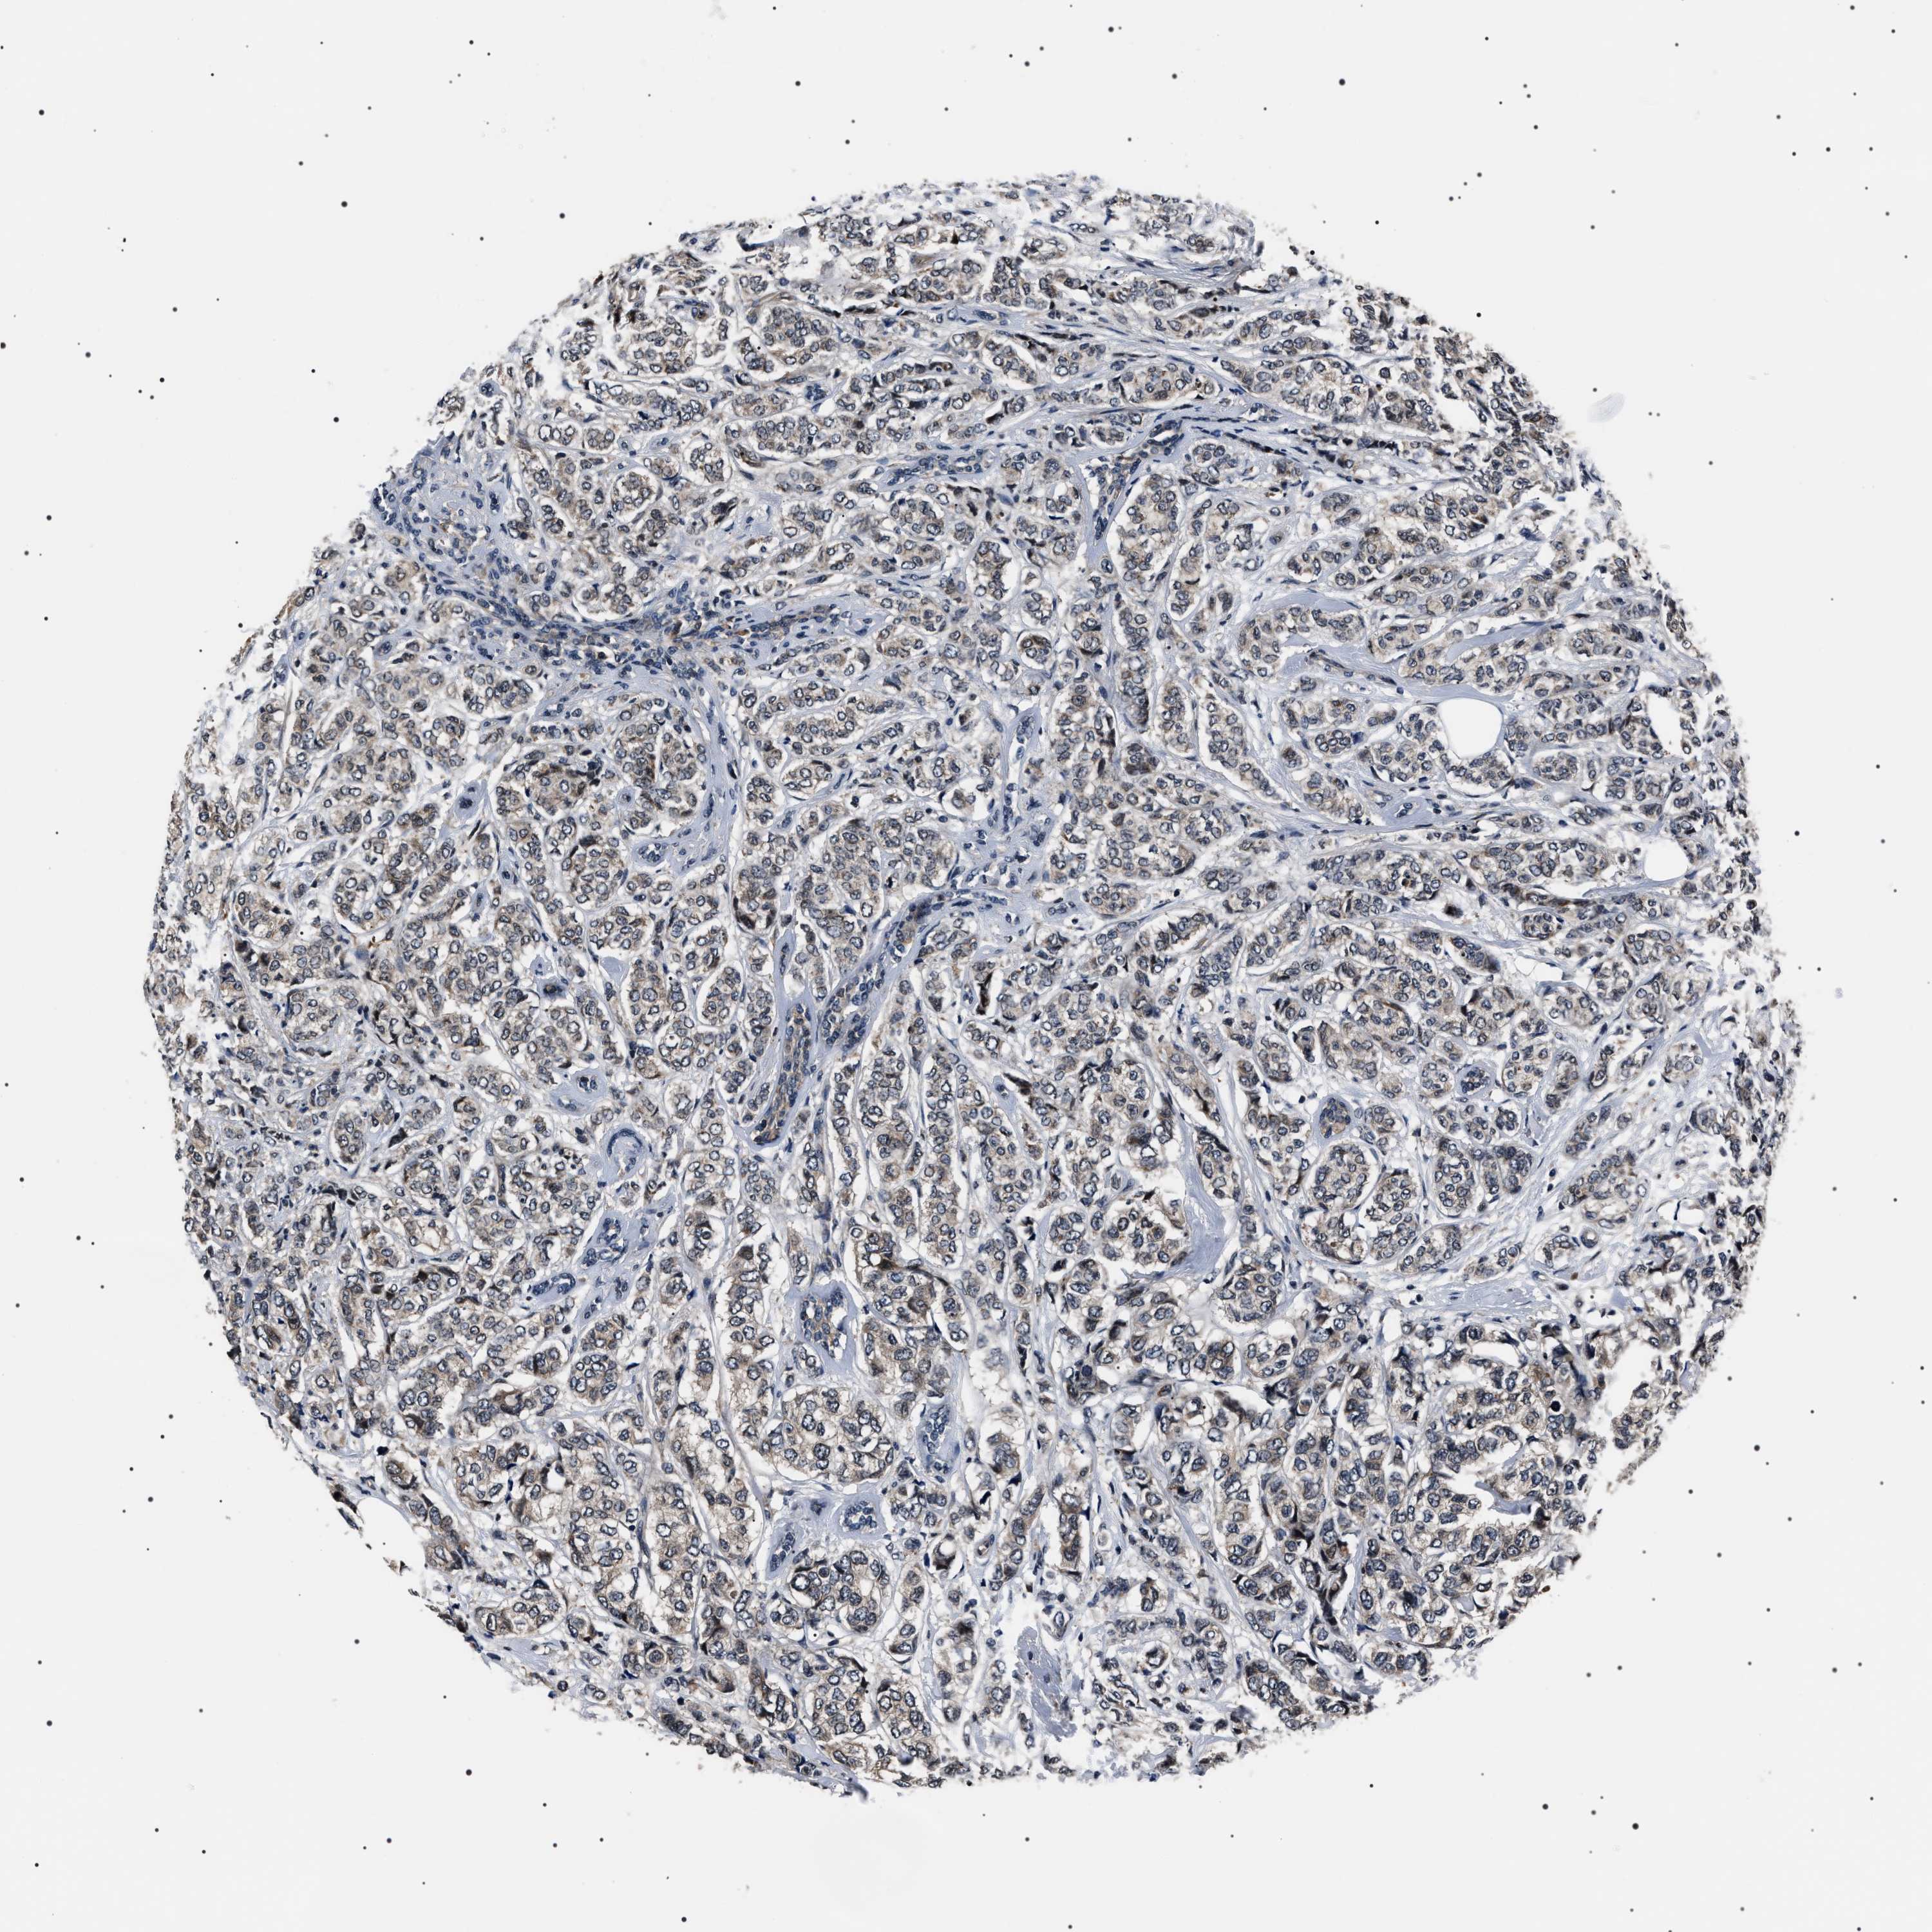

CANCER BREAST CANCER Show tissue menu

BRCA TCGA BRCA VALIDATION PROTEIN EXPRESSION